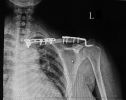

【罕见病例】骨三科成功手术治疗锁骨节段性骨折

在今年收治的患者中,让孙波主任印象最深的是一位53岁的女性患者,这位患者被机动车撞伤,经急诊拍片示:左锁骨远端骨折(见图1)。患者收入院后,孙波主任查体时发现:患者左侧锁骨近端,近胸锁关节处异常“隆起”,并且有压痛及叩击痛,孙波主任又仔细询...